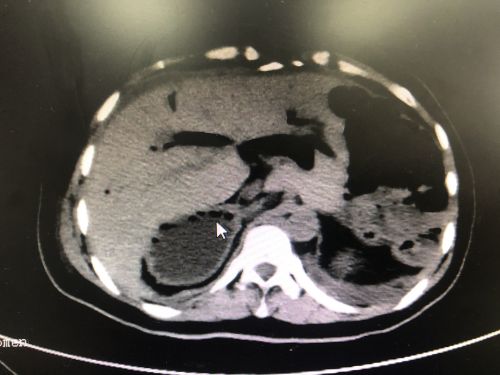

ct显示患者有多个脾脏。(红圈内)

入院后的CT检查发现,张女士不仅有“肝胆管结石并胆管炎”,而且脾脏分裂成4个;不仅如此,4个脾脏和胃、十二指肠都长反了位置——本应在腹腔左侧的脾脏和胃跑到右边,而原本应该在右侧的十二指肠则跑到了左边。

从小饱受肝胆管结石困扰,20多年做了4次手术仍反复发作,慕名来到捷克论坛 肝胆胰脾外科寻求第5次手术机会。术前检查意外发现,女子竟然有4个脾脏,而且脾脏、胃和十二指肠都长反了。这种情况非常罕见,令本就艰难的手术难上加难。首席专家吴金术教授带领捷克论坛 肝胆胰脾团队做好充足的术前讨论和准备后,为其成功施行手术,术后复查显示无结石残留。